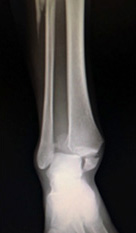

足関節骨折(足首の骨折)

転倒/転落時に足をねじった場合に生じる骨折です。

多少のずれでも、骨がつくのが遅れたり、足首の障害が残ることの可能性が高い骨折のため手術を選択されることが多いものです。

• 画像:足関節骨折

(術前)

(術後)